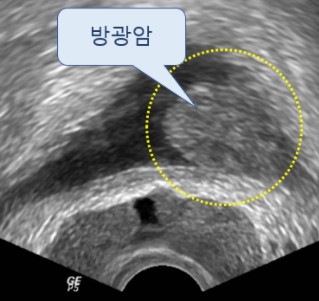

오늘은 남성의 건강을 지키는 중요한 기관, 전립선에 좋은 음식에 대해 이야기하려 합니다. 전립선은 방광 아래에 위치하며 정액을 구성하는 액체를 생산하는 기관입니다.